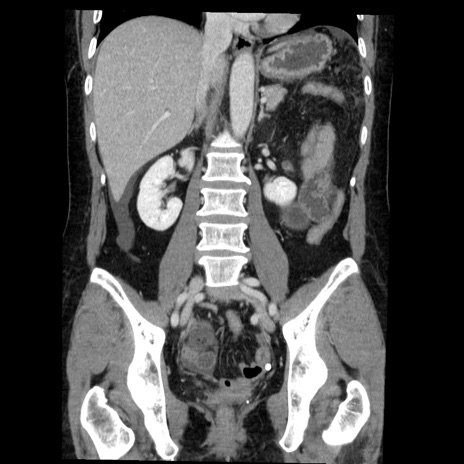

症例6(冠状断像)

【症例】50歳代女性

【主訴】下腹部痛

【既往歴】卵巣癌術後(8年前に当院で卵巣摘出)